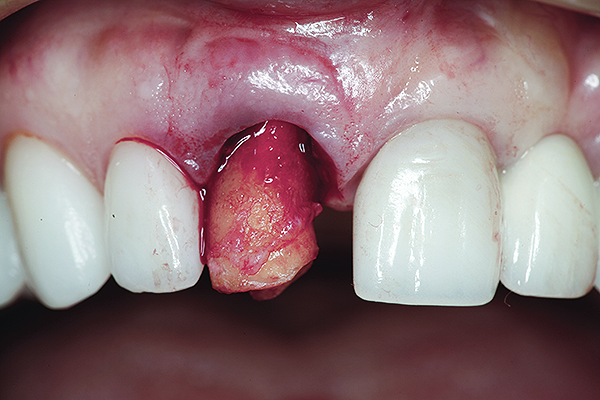

Fig 16. Try-in of the definitive titanium-nitride–coated abutment.

Figure 16

The master cast and abutment were returned to the laboratory for fabrication of the restoration (Figure 15). An all-ceramic crown (e.max®, Ivoclar Vivadent) was fabricated on the custom abutment; it matched the contours of the adjacent central incisor. After completion of custom shading, the definitive abutment and crown were returned to the restorative dentist. The abutment was tried in (Figure 16), and a radiograph was taken to confirm complete seating between the abutment/implant and the crown/abutment. The definitive abutment screw was torqued to 20 Ncm, and the screw-access opening was blocked out with Teflon tape.

The crown was inserted and secured with a luting composite (Multilink® Automix, Ivoclar Vivadent) (Figure 17); a radiograph confirmed complete removal of excess cement (Figure 18). At the 4-month follow-up appointment, the soft tissues were healed within normal limits, and the patient was pleased with the esthetic outcome of the definitive restoration (Figure 19 and Figure 20).